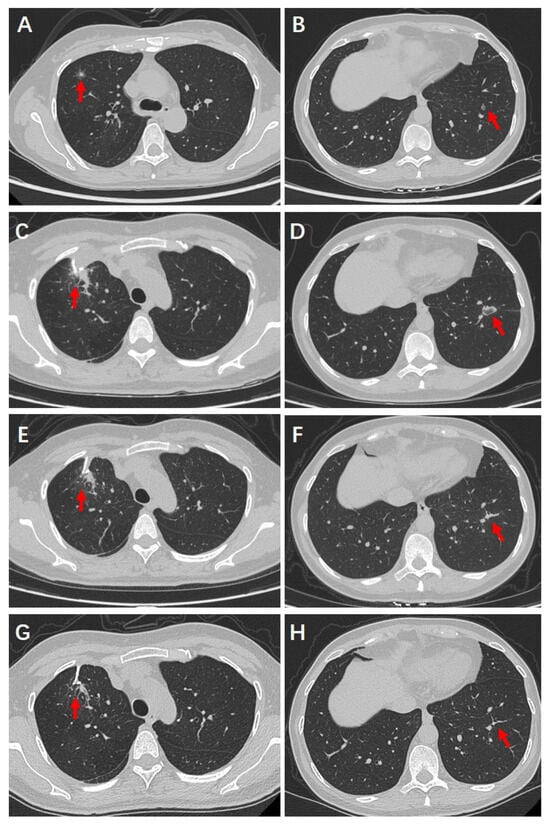

4. Case Report

4.1. Clinical History

4.2. Preoperative Examinations

4.3. Surgical and Ablative Management

4.4. Postoperative Recovery and Follow-Up Outcomes